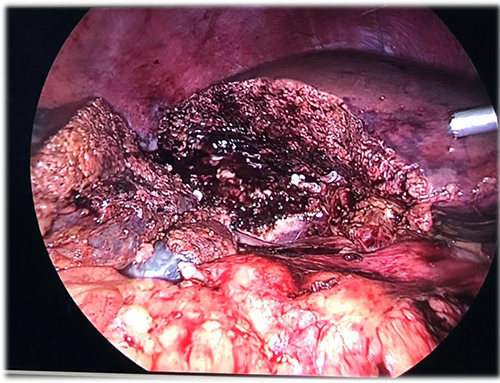

右肝巨大肝血管瘤---S56巨大肝血管瘤切除